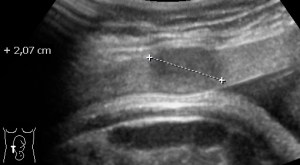

Multiple Myomas in pregnancy 4